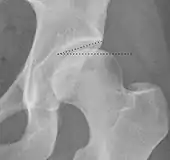

- (C) Shenton line is a continuous arc drawn from the inner edge of the femoral neck to the superior margin of the obturator foramen. In children over about 3 to 4 years of age, this line should be smooth and undisrupted, otherwise it may indicate a fracture or hip dysplasia.[6] However, in infants this line can be unreliable as it depends on the rotation of the hip when the image is taken.[7]